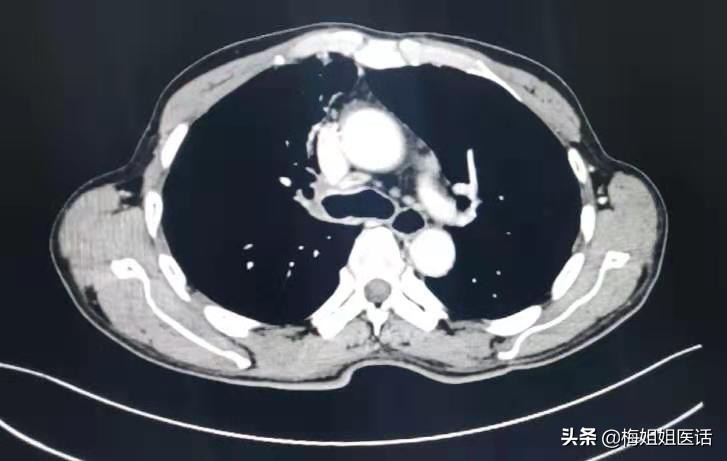

肺癌治疗后

化疗3个周期。胸痛咯血症状消失,状态一天比一天好。才复查评估前期治疗疗效。可以看到治疗后病变明显好转(红圈里的肿瘤几乎消失了)。病情缓解。